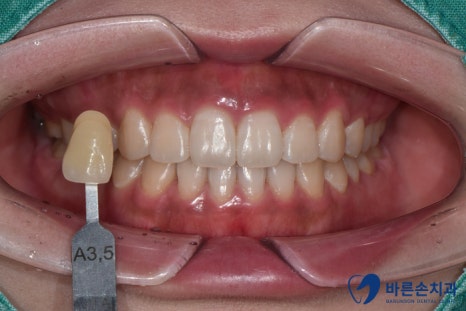

오늘도 간단한 원데이 치아미백 케이스

몇개를 소개드리려고 합니다.

< Case 1>